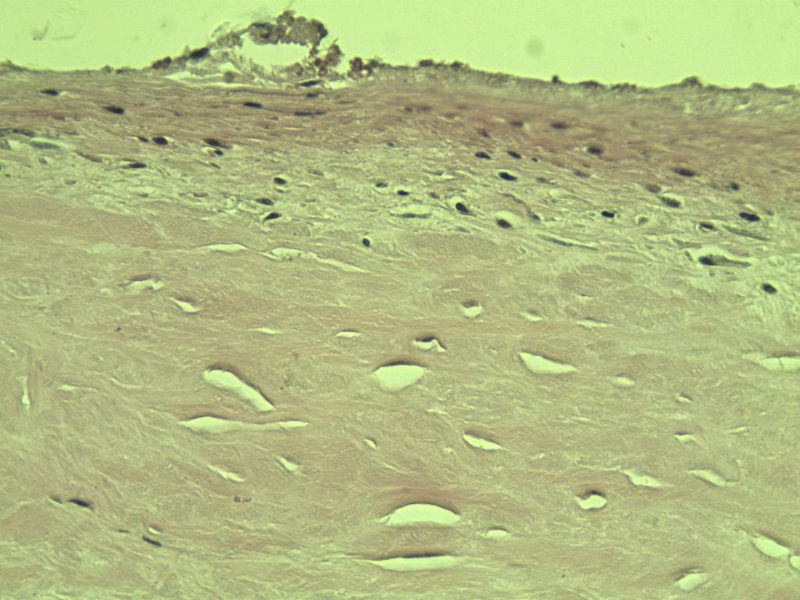

男,51岁, 4月前患者无意中发现右腘窝一包块,约核仁大小无疼痛, 4月来包块进行性生长

灰褐类圆形包块一个,直径 5 cm,切面灰白,实性,编织状。 请各位老师看看 是什么? 谢谢!